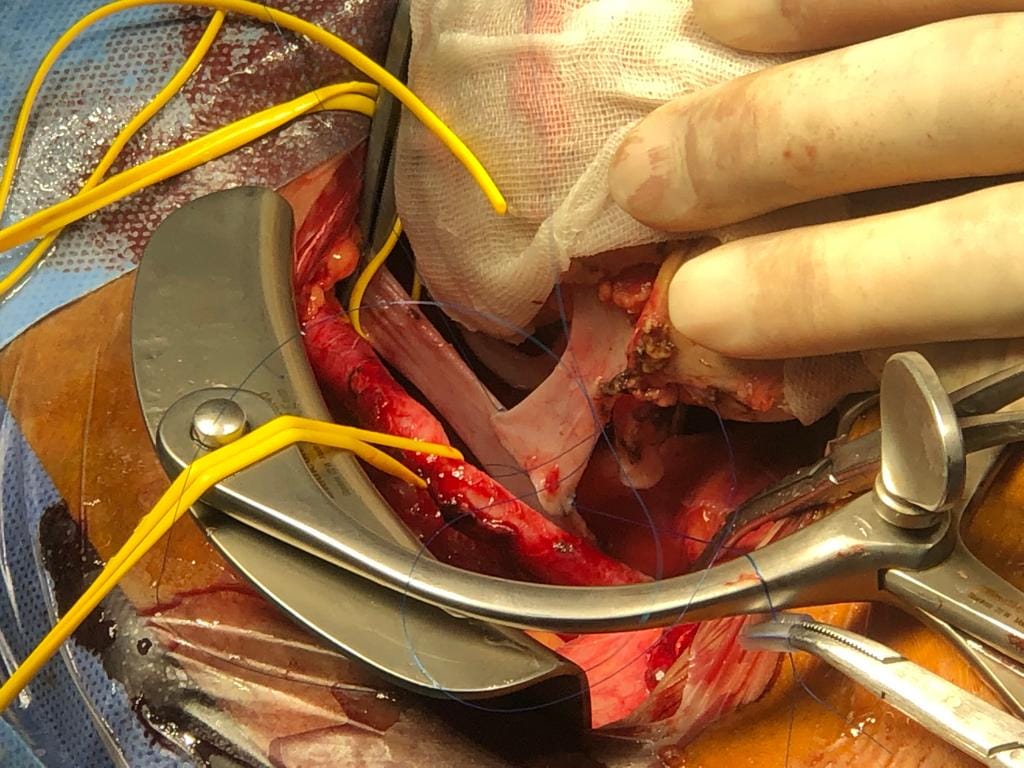

وكشف الدكتور هشام مختار حمودة مدير وحدة زراعة الكلى أن الحالة رقم 48 كانت زراعة كلى لشاب يبلغ من العمر 23 عام وبتبرع من والده الذى يبلغ من العمر 45 عام، والتى كانت عملية حرجة ومعقدة لوجود جلطة متكلسة بأوردة الطرف السفلى الأيمن ممتدة إلى الوريد الاجوف السفلى حتى مستوى قريب من الكليتين الأصليتين وهى ما تعتبر أحدى الحالات النادرة جداً وتمثل تحدياً للفريق الطبي الجراحي .

مضيفاً أن الحالة رقم ٤٩ تمت لشاب عمره ٢٣ سنة أيضا وكانت المتبرعة أخت المريض ذات ٢٢ عاما وكانت هذه الحالة تحدياً خاصاً حيث كان المريض لديه نسبة أجسام مضادة اعلي من المعتاد قبل العملية وهو ما يجعله أكثر عرضة لرفض الكلية المزروعة مما يمثل صعوبة تهدد نجاح الجراحة مما استدعى إعطاء ادوية مثبطة للمناعة خاصة وقوية قبل وأثناء وبعد العملية وتم وبفضل الله التعامل مع الحالة بمهنية وسياسة علمية صحيحة وبإرادة قوية من الفريق للنجاح وحرصهم على توفير الرعاية الصحية السليمة لهذا المريض.

وكشف الدكتور هشام حمودة عن خروج المرضى من المستشفى بوظائف كلى طبيعية ، متوجهاً بشكره إلى كافة أعضاء الفريق الطبي من أساتذة وأطباء متخصصين فى مجالات جراحة المسالك البولية والتخدير والباطنة وبتعاون أطباء الأشعة والباثولوجيا الإكلينيكية والصيدلة الإكلينيكية وفريق التمريض .